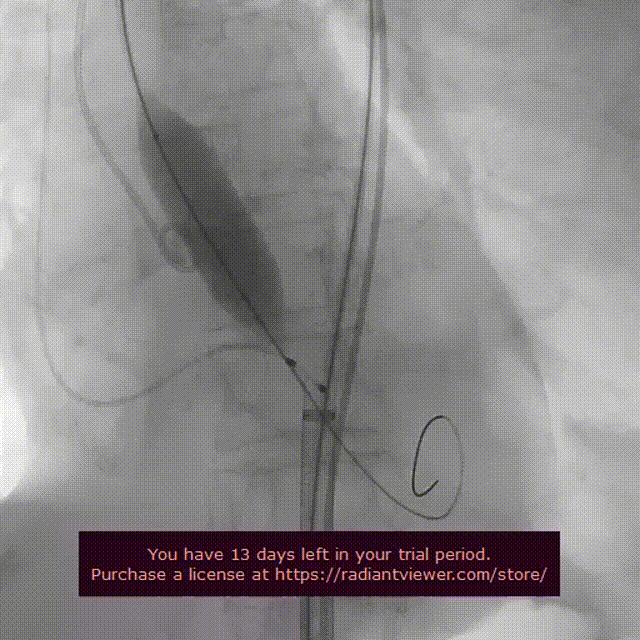

起搏150次/分,VenusA-Plus®L26标准位快速释放,释放至三分之二处,造影发现瓣膜位置不佳,下滑严重,快速进行回收,重新定位释放,造影发现第二次释放位置良好。

瓣膜第二次释放造影

释放后造影观察反流消失,测压显示压差由术前的56mmhg下降至仅8mmhg。

瓣膜释放完毕后造影